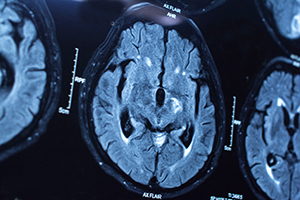

Think about this: Good brain health is about learning the proper way to feed, nurture and strengthen your brain, while eliminating activities that can do it harm.

That’s one of the central themes of #MyBrainHealthMatters, a social media campaign launched in May by the Center for BrainHealth at The University of Texas at Dallas.

Sandra Chapman, Ph.D., founder and chief director for the Center for BrainHealth, said the campaign’s “biggest message is our health begins, and ends, with our brain health.”

#MyBrainHealthMatters is designed to shift the way we think and act about our brains, emphasizing that even subtle changes in our lifestyles can help nurture brain health.

Good brain health is the focus of the #MyBrainHealthMatters social media campaign. Photo: iStock

Many people don’t think about their brains until it is injured, diseased or shows the impact of aging, Chapman said. Improving brain health also is something that healthy people should address, as well.

Chapman said the campaign reinforces the good things that people can do for their brains while dispelling some of the myths about brain health.

Chapman said that the “downside is that chronic multitaskers have a shrunken hippocampus,” part of the brain that is believed to be the center of emotion, memory, and the autonomic nervous system.

“The brain is more complex than physical exercise, and we teach people steps to take that are shown to strengthen neural connections and increase metabolic strength,” Chapman said.